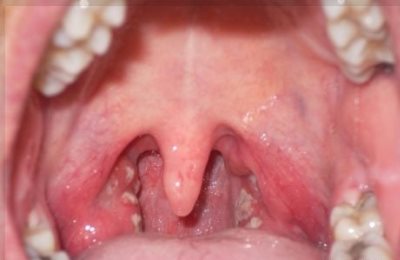

Першение — довольно неприятное ощущение, обычно сопровождающееся кашлем. Щекотание в горле может быть вызвано несколькими причинами. Самая частая из них — фарингит: вирусное или бактериальное воспаление горла или глотки.

При фарингопатии горло отекает, возникает ощущение наличия инородного тела внутри, вызывающее кашель, неприятные ощущения в ушах. При ларингите горло сильно болит, человеку трудно глотать и даже дышать.

Такие же симптомы наблюдаются при трахеите, но при этом еще щекочет в горле, присутствует кашель и ощущение царапанья, зуда в глотке и ушах.

К симптомам таких заболеваний относится повышение температуры, воспалительные процессы в области надгортанника и окружающих тканей, нарушения проходимости дыхательных путей, заложенность в ушах.